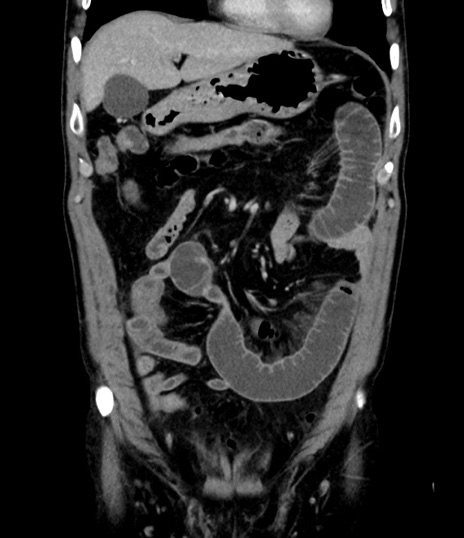

症例8(冠状断像)

【症例】 60歳代男性

【主訴】 黒色吐物

【現病歴】 4日前から嘔気自覚、2日前の朝食後にも嘔気あり、自分で手で嘔吐反射起こし嘔吐したところ血が混ざっていたため受診。

【既往歴】 5年前汎発性腹膜炎を伴う急性虫垂炎で手術、高血圧、前立腺肥大症、高脂血症

【身体所見】 腹部正中に手術癩痕あり 腹部平坦・軟圧痛なし膨満感あり

【データ】WBC 8400、CRP 4.54